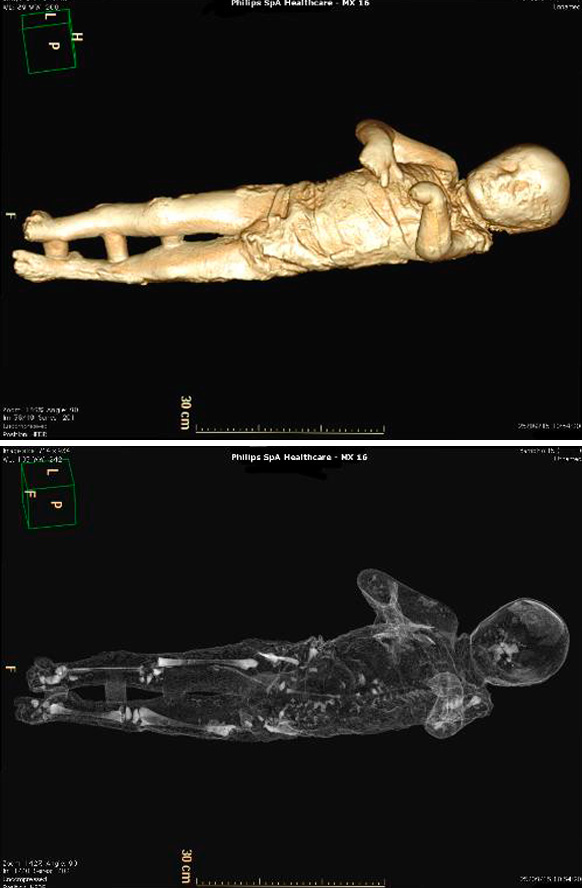

Por primera vez, un grupo de moldes de yeso de Pompeya ha sido sometido a tomografías axiales computerizadas (TAC), a partir de las que ha sido posible determinar la edad, las patologías médicas, los hábitos alimentarios y el estilo de vida de los habitantes de la ciudad arrasada por el Vesubio en el 79 d.C.

El objetivo del estudio radiológico ha sido obtener imágenes del interior de los cuerpos que quedaron conservados en ceniza durante la erupción del volcán, y que luego fueron rellenados con yeso con el propósito de preservar su integridad.

Asimismo, han sido realizados relieves en tres dimensiones de todos los cuerpos mediante técnicas digitales de vanguardia que permiten obtener datos sobre cómo ha variado su estado de conservación en el tiempo.